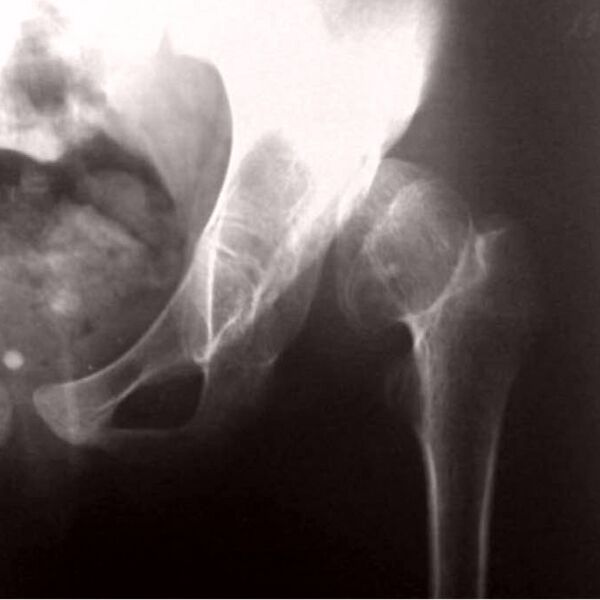

Псевдоартро́з (либо «неоартро́з») — это ложный сустав, образовавшийся на несвойственном ему месте вследствие длительно существующего вывиха, либо длительно не сросшегося перелома при отсутствии должной медицинской помощи. Он образуется, как правило, после трёх—шести месяцев после травмы[1].

В некоторых случаях ложный сустав формируется как паллиативная операция при лечении травмы, например, при переломе шейки бедра у пожилых пациентов, когда невозможно или недоступно эндопротезирование.

Диагноз ставится на основании рентгеновских снимков в двух взаимно перпендикулярных проекциях и клинических проявлений.